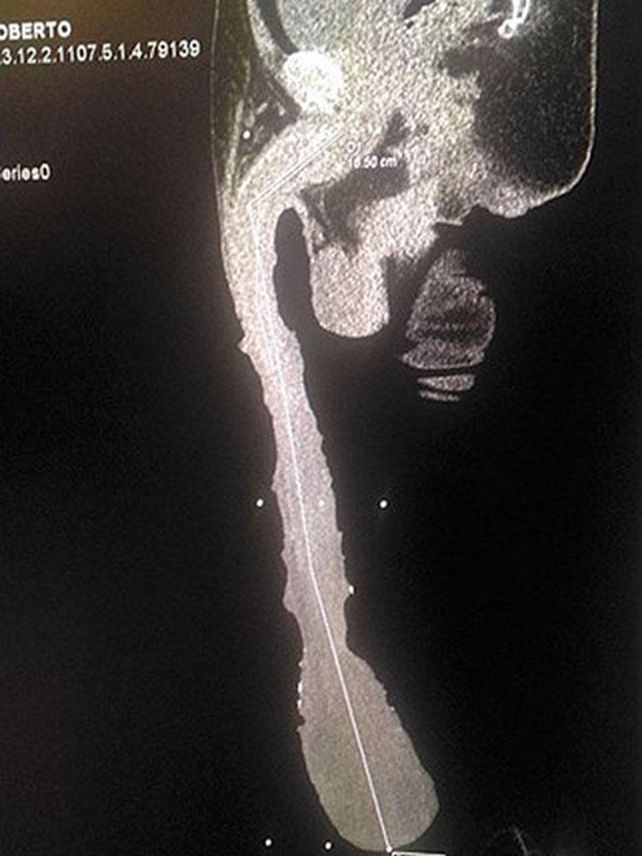

El mexicano Roberto Esquivel Cabrera acudió a las oficinas del diario Vanguardia en Saltillo, Coahuila, México, para dar a conocer que no tiene trabajo por su extraña condición: porta un pene de 48,2 centímetros de largo, con una circunferencia del glande de 25 centímetros.Ahora, busca conquistar el récord Guinness como el hombre que tiene el miembro más grande del mundo.

De acuerdo al diario 24 Horas, un equipo clínico decidió tomar el caso del mexicano para saber si su condición se presentó por ingerir algún medicamento o por algún truco para tener el miembro de ese largo.

La conclusión de los médicos fue que era completamente natural. "Mire hasta dónde me llega, debajo de las rodillas. No puedo hacer nada, no puedo trabajar, soy un discapacitado", dijo Esquivel Cabrera.Actualmente Jonah Falco ostenta el título del hombre con el pene más grande del mundo, con 34 centímetros.Fuente: Vanguardia